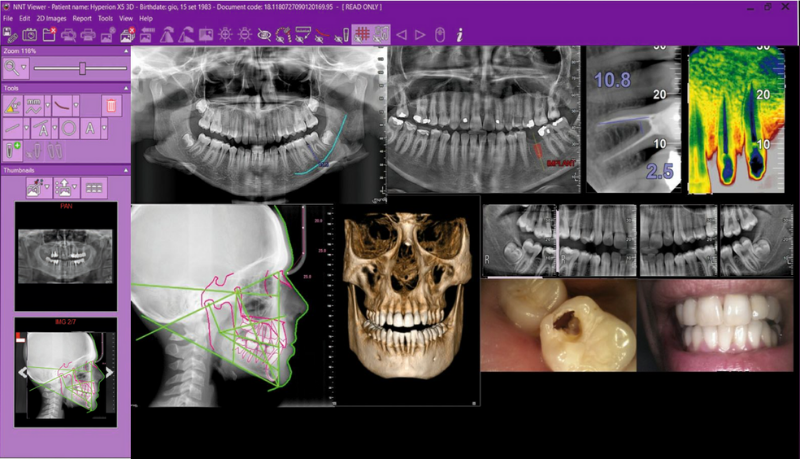

MULTI-DESKTOP 3D/2D

Un logiciel unique pour gérer et traiter des images 3D et 2D. Le système multi-bureaux permet de naviguer rapidement entre les différentes vues du 2D au 3D avec un rendu réaliste et des analyses multiplan panoramiques. Tout le nécessaire pour un diagnostic de qualité et une communication rapide avec le patient.

BIBLIOTHÈQUES D’IMPLANTS PRÉCHARGÉ

iRYS facilite la sélection et le positionnement des implants préférés parmi ceux présents dans sa vaste bibliothèque. Il est en outre possible de les modifier et d’en ajouter de nouveaux en quelques étapes simples.

Un set complet d’outils pour tous vos diagnostics.

Des diagnostics et une planification simple et efficace grâce aux meilleurs protocoles et filtres du logiciel iRYS.

Planification implantaire avancée

Définissez la position de l’implant directement sur le modèle 3D, combinez-le avec les données STL provenant de scanners intra-oraux, et déterminez le projet prothétique définitif. Avec les instruments de planification implantaire avancée, vous pourrez opérer en toute sécurité, grâce aux informations précises sur la quantité d’os et la distance par rapport aux structures anatomiques avoisinantes, comme le canal mandibulaire, en définissant une distance minimale de sécurité.